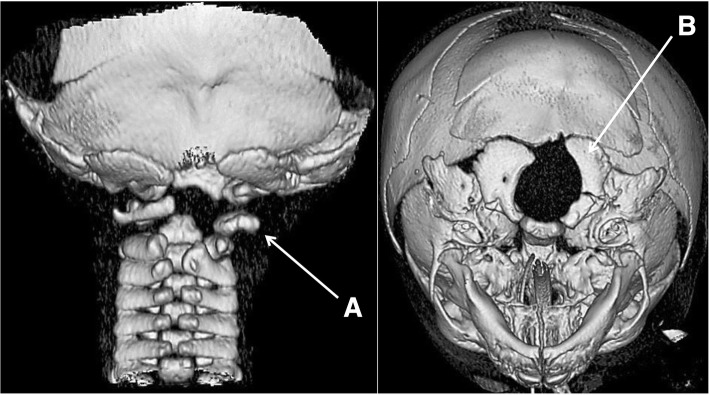

Fig. 2.

3D bone CT reconstruction showing hypoplasia of the posterior hemiarches of C1-C2 (a) and the right exo-occipital bone (b) and a small clivus

Focal lesions, whether associated or not with abnormalities of the vertebrobasilar arterial system, have led to the alternative hypothesis of an acquired, i.e. disruptive, mechanism [19]. The previously described vascular abnormalities in brainstem disconnection were mainly the absence or the extreme hypoplasia of the vertebral or basilar arteries [20]. In our case, MR angiography demonstrated hypoplasia and parietal irregularities of the proximal segments and absence of the distal segments of the right vertebral artery. The unilateral, well-defined, elliptical anteroposterior lesion of the cervico-medullary junction in our patient may be consistent with intrauterine ischaemia, but the precise timing of the insult is difficult to establish. During the early embryonic period, the posterior circulation is exclusively supplied by the internal carotid arteries through a series of anastomoses that will regress with the development of the vertebrobasilar arterial system [25]. The trigeminal, otic and hypoglossal arteries intervene in the formation of the basilar artery. The cervical portion of the vertebral artery, i.e. the V1 and V2 segments, is formed by anastomoses from the first six cervical intersegmental arteries, while the proatlantal intersegmental artery contributes to the formation of the V3 and V4 segments. In our patient, the lack of visualization of the V3 and V4 segments of the right vertebral artery on MR angiography may be explained by early occlusion or agenesis of the proatlantal artery. However, the origins of these vascular abnormalities may also be dysplastic or inflammatory, in parallel with the vascular involvement observed as early as 12 weeks of gestation at the level of placenta. Moreover, the resulting ischaemia may have caused the focal defect at the medullary level, the homolateral hypoplasia of the exo-occipital bone, and the lateral mass of C1. Indeed, these last two elements probably have a common embryological origin, from the fourth occipital and the first spinal sclerotomes, and they are also perfused by the proatlantal artery [26]. The hypoplasia of the right transverse process of C2 might be related to the hypoplasia of segments V1 and V2, its blood supply being provided by the first intersegmental cervical artery [27]. Other causes of disruptions, such as alcohol or cocaine exposure during pregnancy, have also been described in brainstem disconnection [28, 29]. Nevertheless, the controversy concerning a malformative or vascular origin of this condition has not yet been resolved. The involvement of genes critical for both the formation of the brainstem and its vascularization should also not be excluded [22].